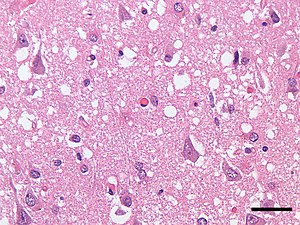

![]() | |

| Micrograph showing spongiform degeneration (vacuoles that appear as holes in tissue sections) in the cerebral cortex of a patient who had died of a prion disease (Creutzfeldt-Jakob disease). H&E stain. Scale bar = 30 microns (0.03 mm). | |

Prions cause neurodegenerative disease by aggregating extracellularly within the central nervous system to form plaques known as amyloids, which disrupt the normal tissue structure. This disruption is characterized by "holes" in the tissue with resultant spongy architecture due to the vacuole formation in the neurons.[66] Other histological changes include astrogliosis and the absence of an inflammatory reaction.[67] While the incubation period for prion diseases is relatively long (5 to 20 years), once symptoms appear the disease progresses rapidly, leading to brain damage and death.[68] Neurodegenerative symptoms can include convulsions, dementia, ataxia (balance and coordination dysfunction), and behavioural or personality changes.[citation needed]